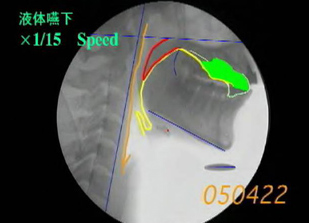

さまざまな疾病や加齢による機能低下を原因とする摂食・嚥下機能障害に対する診断、治療、リハビリテーション指導を行っている。必要があれば訪問治療にも対応する。また、地域の医療機関との連携も行っている。